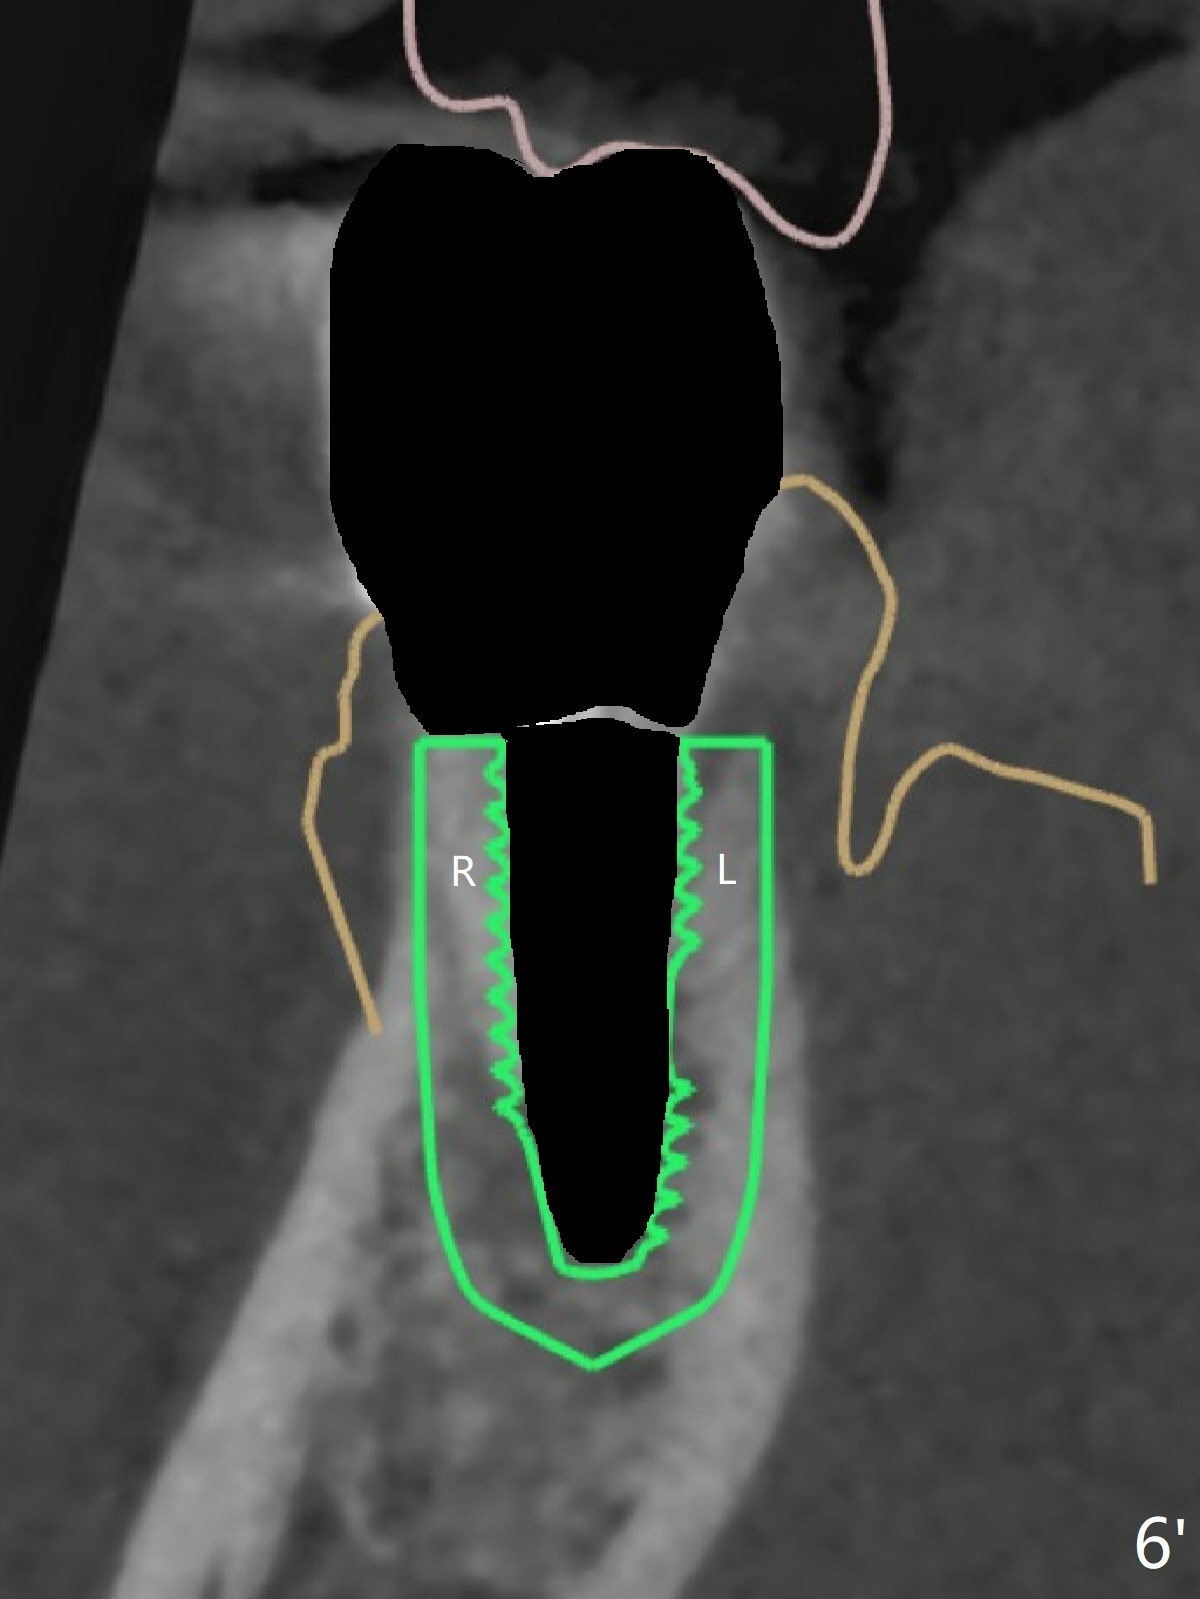

A 42-year-old man has been our patient for 3-4 years (Fig.1). An asymptomatic fistula develops lingual to the tooth #21 (Fig.2). An oblique fracture line appears to be next to a post (Fig.3 ^). A 3.5x11.5 mm implant seems to be able to be placed immediately lingual to the thick lingual plate with guide (Fig.4 L). No buccal deviation will occur with sufficient buccal gap. Design of an immediate implant at #21 (coronal section, Fig.5). In fact the root remains in place first (i.e., extract the crown first, Fig.5'). When osteotomy is done with the last drill 4x11.5 mm, there will be no deviation because of even counteraction between the buccal root and the lingual plate (Fig.6'). Then the root will be removed. But the 4.5x11.5 mm implant may be deviated buccal because of implant engagement into the lingual plate without buccal counteraction. Therefore, a 4x13 mm implant will be placed following 3.5x13 mm (last) drill. The implant is placed between the mesial and distal walls (Fig.7 sagittal section).